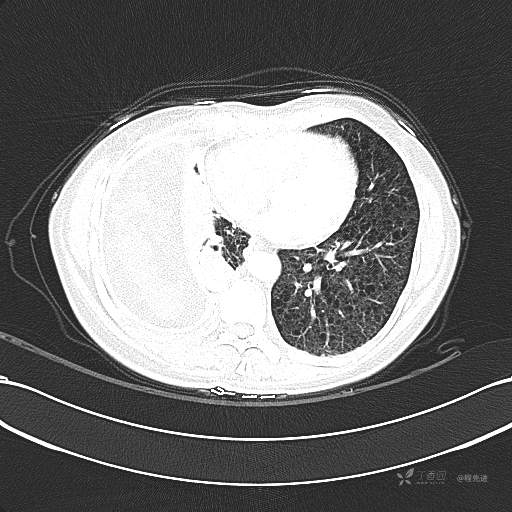

患者性别:女

患者年龄:51岁

简要病史:胸闷半年